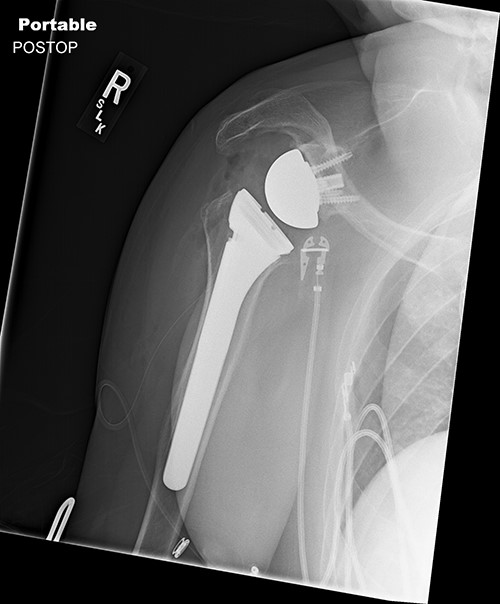

Surgically implanted devices included the DePuy France Delta Xtend Total Shoulder System, standard metaglene, standard glenosphere, cementless modular humeral stem, cementless modular epiphysis, standard humeral polyethylene cup, locking metaglene screw and non-locking metaglene screw.

Standard metaglene was positioned superiorly within the glenoid fossa to accommodate a 145° epiphysis and +4-mm lateralized glenosphere (Figs 4 and 5). There were no intraoperative complications.